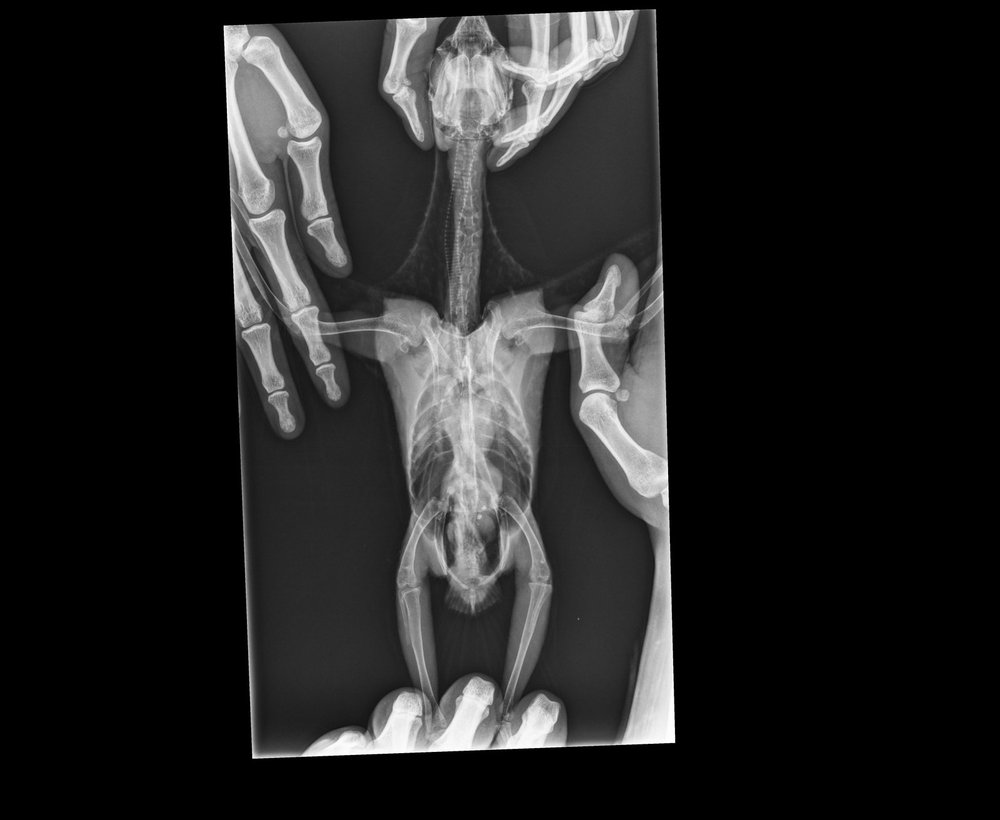

KamaRo Опубликовано 28 ноября, 2018 #8 Опубликовано 28 ноября, 2018 @Nadea про Аронову спросила, т.к. подумала, что она в декрете и сейчас прием не ведет. Аронова стажируется у Волгиной, что говорит о стремлении доктора постоянно расти. А с птицами всегда тяжело, много чего остается за нашим пониманием (не все виды исследований доступны, как у кошек/собак). Если вы у другого врача наблюдались, то о нем тоже хорошие отзывы не помешали, чтобы владельцев птиц направлять к специалисту. При сильном нарушении в работе органов, в т.ч. ЖКТ нужно препараты давать в клюв, с едой мало попадает по назначению. У вас и антибиотики были и довольно тяжелый для печени препарат - орунгал, поэтому лечить уже в комплексе нужно (и гепатопротекторы принимать, и про-пребиотики). Не плохо работают при нарушении микрофолоры - споровит+бифидо-и лактобактерии, фортифлора+бифидо-и лактобактерии, были не плохие результаты на энтероле+пробиотик. Просто какой то метод выбирают и дают в клюв. Споровит (в жидком виде) по 0,3 мл 2 раза в день, методом подбора лакто-и бифидосодержащий пробиотик (мне всегда нравился бифидумбактерин - там 5 доз, на волнушку на глаз флакон делила на 8 приемов, шпажкой откалывала, разводила водой и выпаивала), на амазона наверное 1/2 флакона на 2 приема (утро-вечер). Что касается гепатопроткторов, то их еще с месяц дают после противомикробных препаратов и тоже в клюв. Шрот расторопши в данном случае не особо помогут - это полезная добавка, но в качестве самостоятельного компонента не справится. Гептрал может быть на гепатовет заменить, но он жутко вонючий, но птицы его вполне не плохо переносят, особенно если на 2 приема разделить (но его нужно разводить, т..к суспензия густая и тяжело выпоить). Сейчас вам нужно восстанавливать птицу.